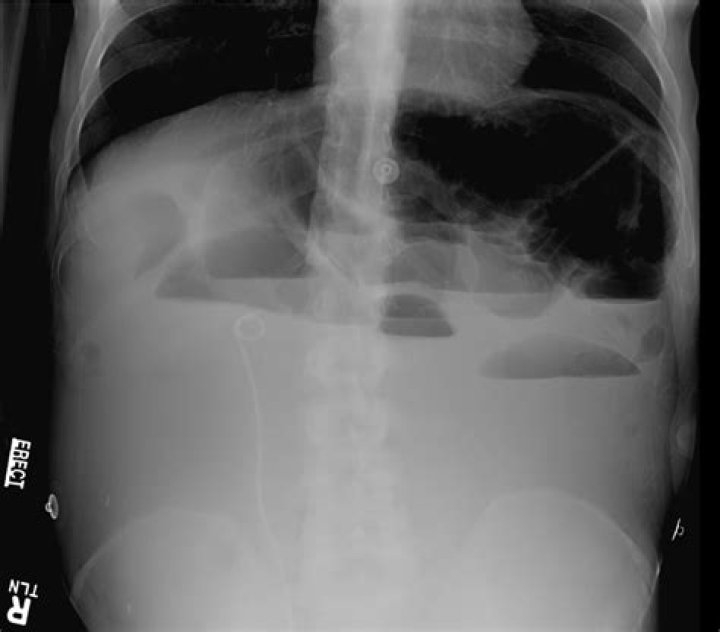

A kidney, ureter, and bladder (KUB) X-ray is also known as a “flat plate of the abdomen x-ray,” may be performed to assess the abdominal area for causes of abdominal pain, or to assess the organs and structures of the urinary and/or gastrointestinal (GI) system.

: a radiograph especially of the abdomen taken with the subject lying flat.

Can an X-ray show an intestinal blockage?

To confirm a diagnosis of intestinal obstruction, your doctor may recommend an abdominal X-ray. However, some intestinal obstructions can’t be seen using standard X-rays. Computerized tomography (CT). A CT scan combines a series of X-ray images taken from different angles to produce cross-sectional images.